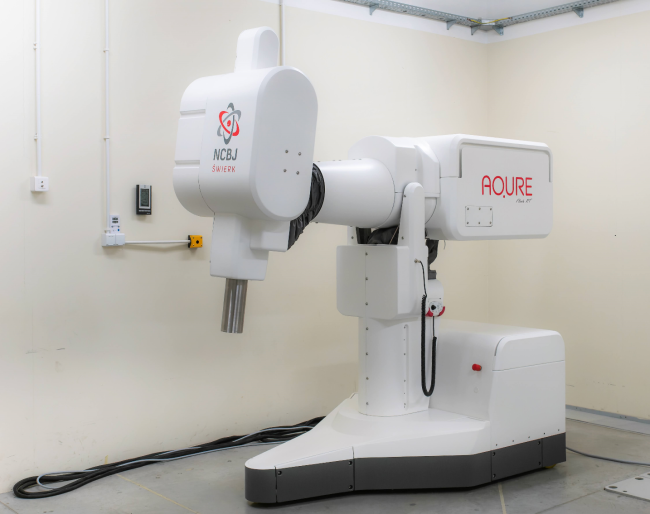

Nowatorski akcelerator AQURE FLASH (RT), opracowany w Narodowym Centrum Badań Jądrowych we współpracy z Wielkopolskim Centrum Onkologii, wykorzystuje ultra wysokie dawki promieniowania i może stać się przełomowym narzędziem w leczeniu nowotworów. Ta innowacyjna technologia już na etapie testów wzbudza duże zainteresowanie i nadzieje w środowisku medycznym. Projekt został właśnie nominowany w plebiscycie „Łączy nas WIELkopolskiE” w kategorii Badania i Rozwój. Internetowe głosowanie rozpocznie się 17 września i potrwa 10 dni.

Warsztaty „Wiązki FLASH w Badaniach” w NCBJ – przyszłość terapii FLASH-RT

6 marca w NCBJ odbyły się warsztaty „Wiązki FLASH w Badaniach – Obecne Badania i Kierunki Rozwoju”. Wydarzenie było poświęcone badaniom naukowym prowadzonym na wytworzonej infrastrukturze w projekcie „Budowa i walidacja stanowiska generującego wiązkę elektronów o ultra wysokiej mocy dawki (FLASH-RT)”.

W dniach 9–10 czerwca na Politechnice Warszawskiej odbył się 2. Kongres Nauka dla Społeczeństwa pod hasłem „Tak nauka w Polsce wpływa na życie każdego człowieka”. W trakcie Kongresu, przedstawiciele Narodowego Centrum Badań Jądrowych prezentowali m.in. jedno z najnowszych wdrożeń Instytutu – Akcelerator AQURE FLASH (RT) o ultra wysokiej mocy dawki.

Akcelerator w poszukiwaniu nowych metod leczenia nowotworów

Terapia FLASH może być obiecującą metodą niszczenia nowotworów, przy jednoczesnym lepszym zachowaniu komórek zdrowych. Zbudowany w NCBJ akcelerator wspomaga już badania nad tym sposobem leczenia w Wielkopolskim Centrum Onkologii.

NCBJ buduje stanowisko generujące wiązkę elektronów o ultra wysokiej mocy dawki (FLASH)

W Zakładzie Aparatury Jądrowej NCBJ, przy współudziale Departamentu Aparatury i Technik Jądrowych NCBJ, została zaprojektowana i zbudowana struktura przyspieszająca akceleratora do nowego stanowiska badawczego terapii typu FLASH. Pionierskie stanowisko ma wykorzystywać konstrukcję akceleratora medycznego AQURE i docelowo ma działać w WCO w Poznaniu.

Artykuł o FLASH doceniony przez SEP

Obiecujące wyniki pierwszych badań i testów radioterapii wykorzystującej ultra wysokie moce dawki, FLASH, powodują, że zainteresowanie ta techniką stale rośnie. Badania w tej tematyce są doceniane, co potwierdza nagroda, jaką uzyskał ostatnio artykuł o terapii FLASH autorstwa naukowców Zakładu Aparatury Jądrowej NCBJ.